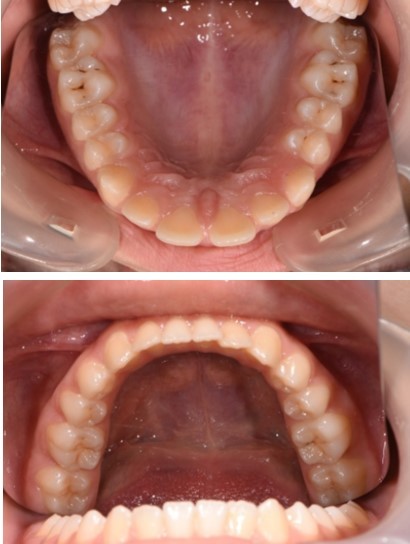

In order to emphasize one of the major indications of skeletal anchorage with mini implants, a clinical case was selected. A young teenage patient (Figure 1, Figure 2, Figure 3, Figure 4), with a severe overjet, flared upper incisors with spacingand a convex profile was reffered to our dental office. Treatment objectives were established from the beggining: retrusion of the upper anterior teeth, overjet and overbite correction, space closure and obtaining a better occlusion. Anchorage needs were evaluated. Absolute anchorage was needed in order to obtain upper dental retrusion without mesial movement of the posterior teeth. Two mini implants were placed bilaterally, in a labial position, between the second premolars and upper first molars. Both mini plates and mini implants provide a predictable result in this case but since mini implants are more easy to place and provide a higher degree of comfort, this option seemed more suitable. In this way, the need for other anchorage devices, such as a palatal arch or headgear was eliminated. The upper incisors and canines can be now distalized and intruded, after the upper premolar extraction.

Figure 2.Initial intraoral view of the case before orthodontic treatment – occlusal view.

Figure 3.Initial intraoral view of the case before orthodontic treatment – occlusal view.